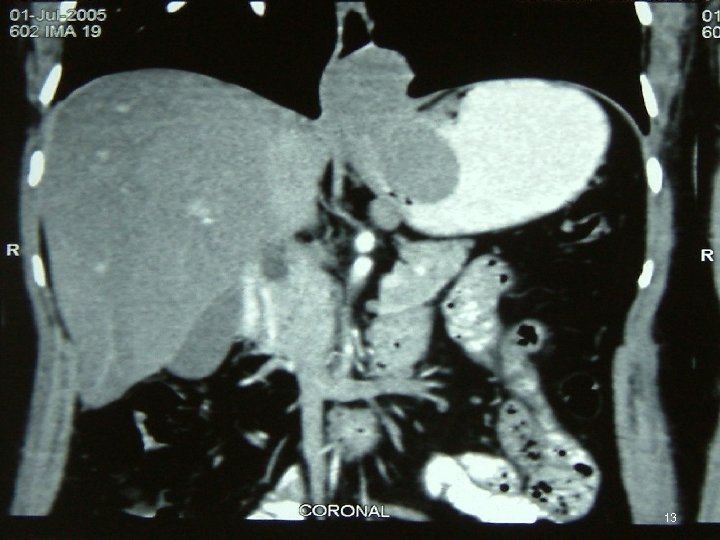

Investigations • • • Chest X Ray USG CECT EUS Ba Swallow 3

Diagnosis • FDG PET = mandatory ►FDG-PET CT scan is ideal • MD-CE-CT = image modality of choice for abdomen (if FDG-PET-CT is not available) • MR • Evaluate by Chol or RECIST criterion 46

Diagnosis • Polyp / Metastases of Lobular Breast CA in Ut • GIST, Lymphoma / 2 nd primary at GI jn